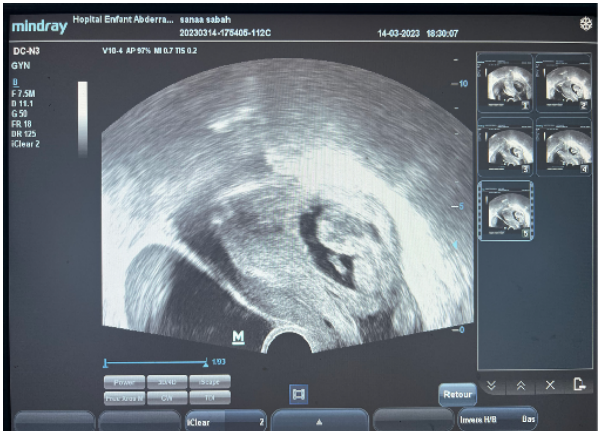

22-year-old patient, nulliparous, with no particular pathological history, admitted to the emergency department for metrorrhagia associated with pelvic pain after 5 months of amenorrhea. Examination revealed a tachycardic patient, BP 90/50 mmhg, generalized mucocutaneous pallor, sweating, slightly distended abdomen with generalized defensiveness, bleeding from the endocervix. Pelvic ultrasound showed an empty uterus of normal size, a retrouterine gestational sac measuring 88x43mm containing a live embryo biometrically estimated to be pregnant at 15 weeks of amenorrhea, associated with a copious effusion (Figure 1), and a BHCG level of 79859. She underwent emergency laparotomy, exploration showed a hemoperitoneum estimated at 2 liters, An ovoid fetal sac measuring 10 cm, implanted directly between the uterus and the rectum, adherent to the omentum at the level of the cul de sac of the Douglas (Figure 2, Figure 3).

Figure 1: Transvaginal ultrasound showing a retrouterine gestational sac with a live embryo, consistent with secondary abdominal pregnancy at 15 weeks of amenorrhea.